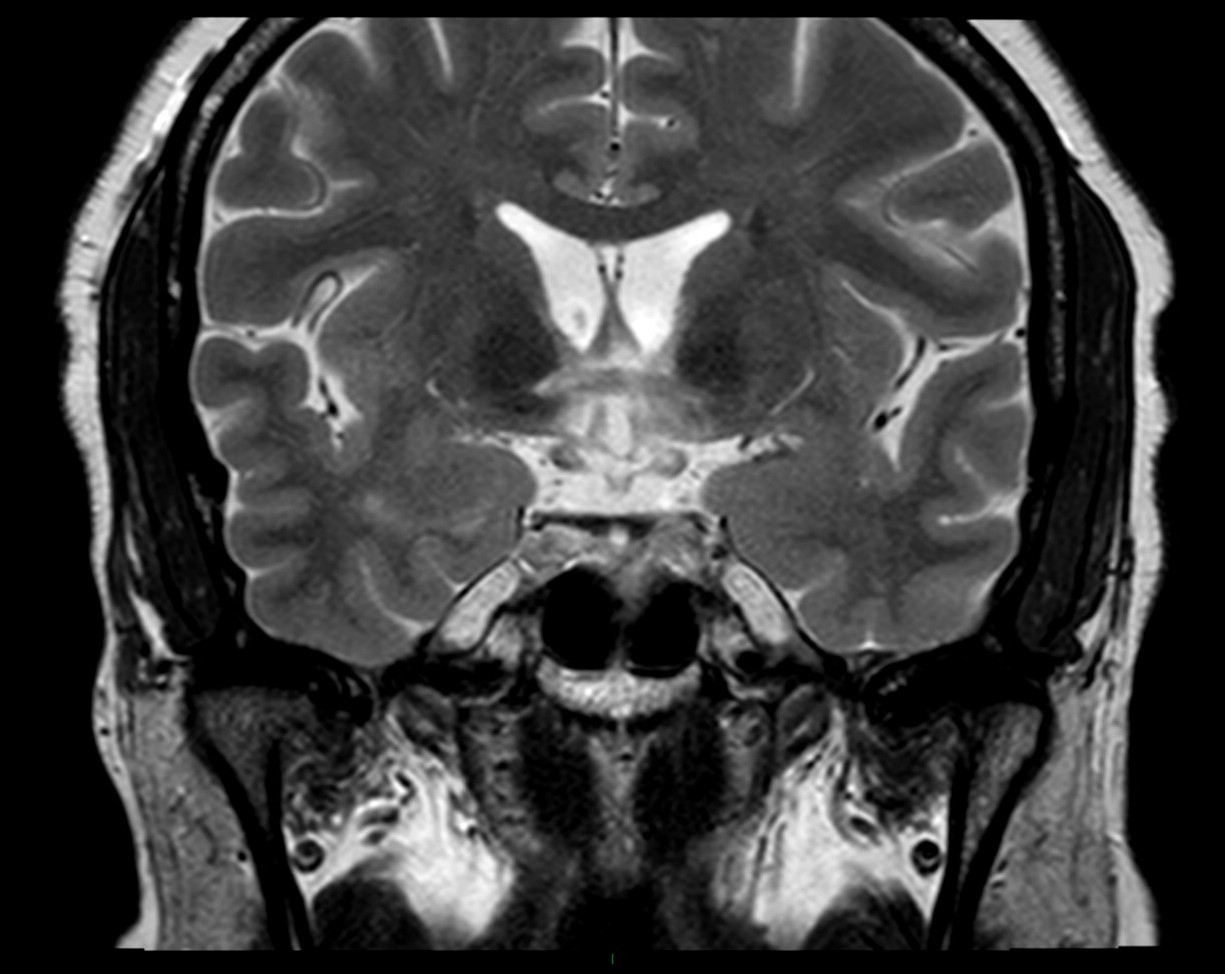

Publié 10 mars 2015 à 1225 × 974 dans Sclérose en plaque et pathologies démyélinisantes

Hypersignal hypothalamique bilatéral et du chiasma optique